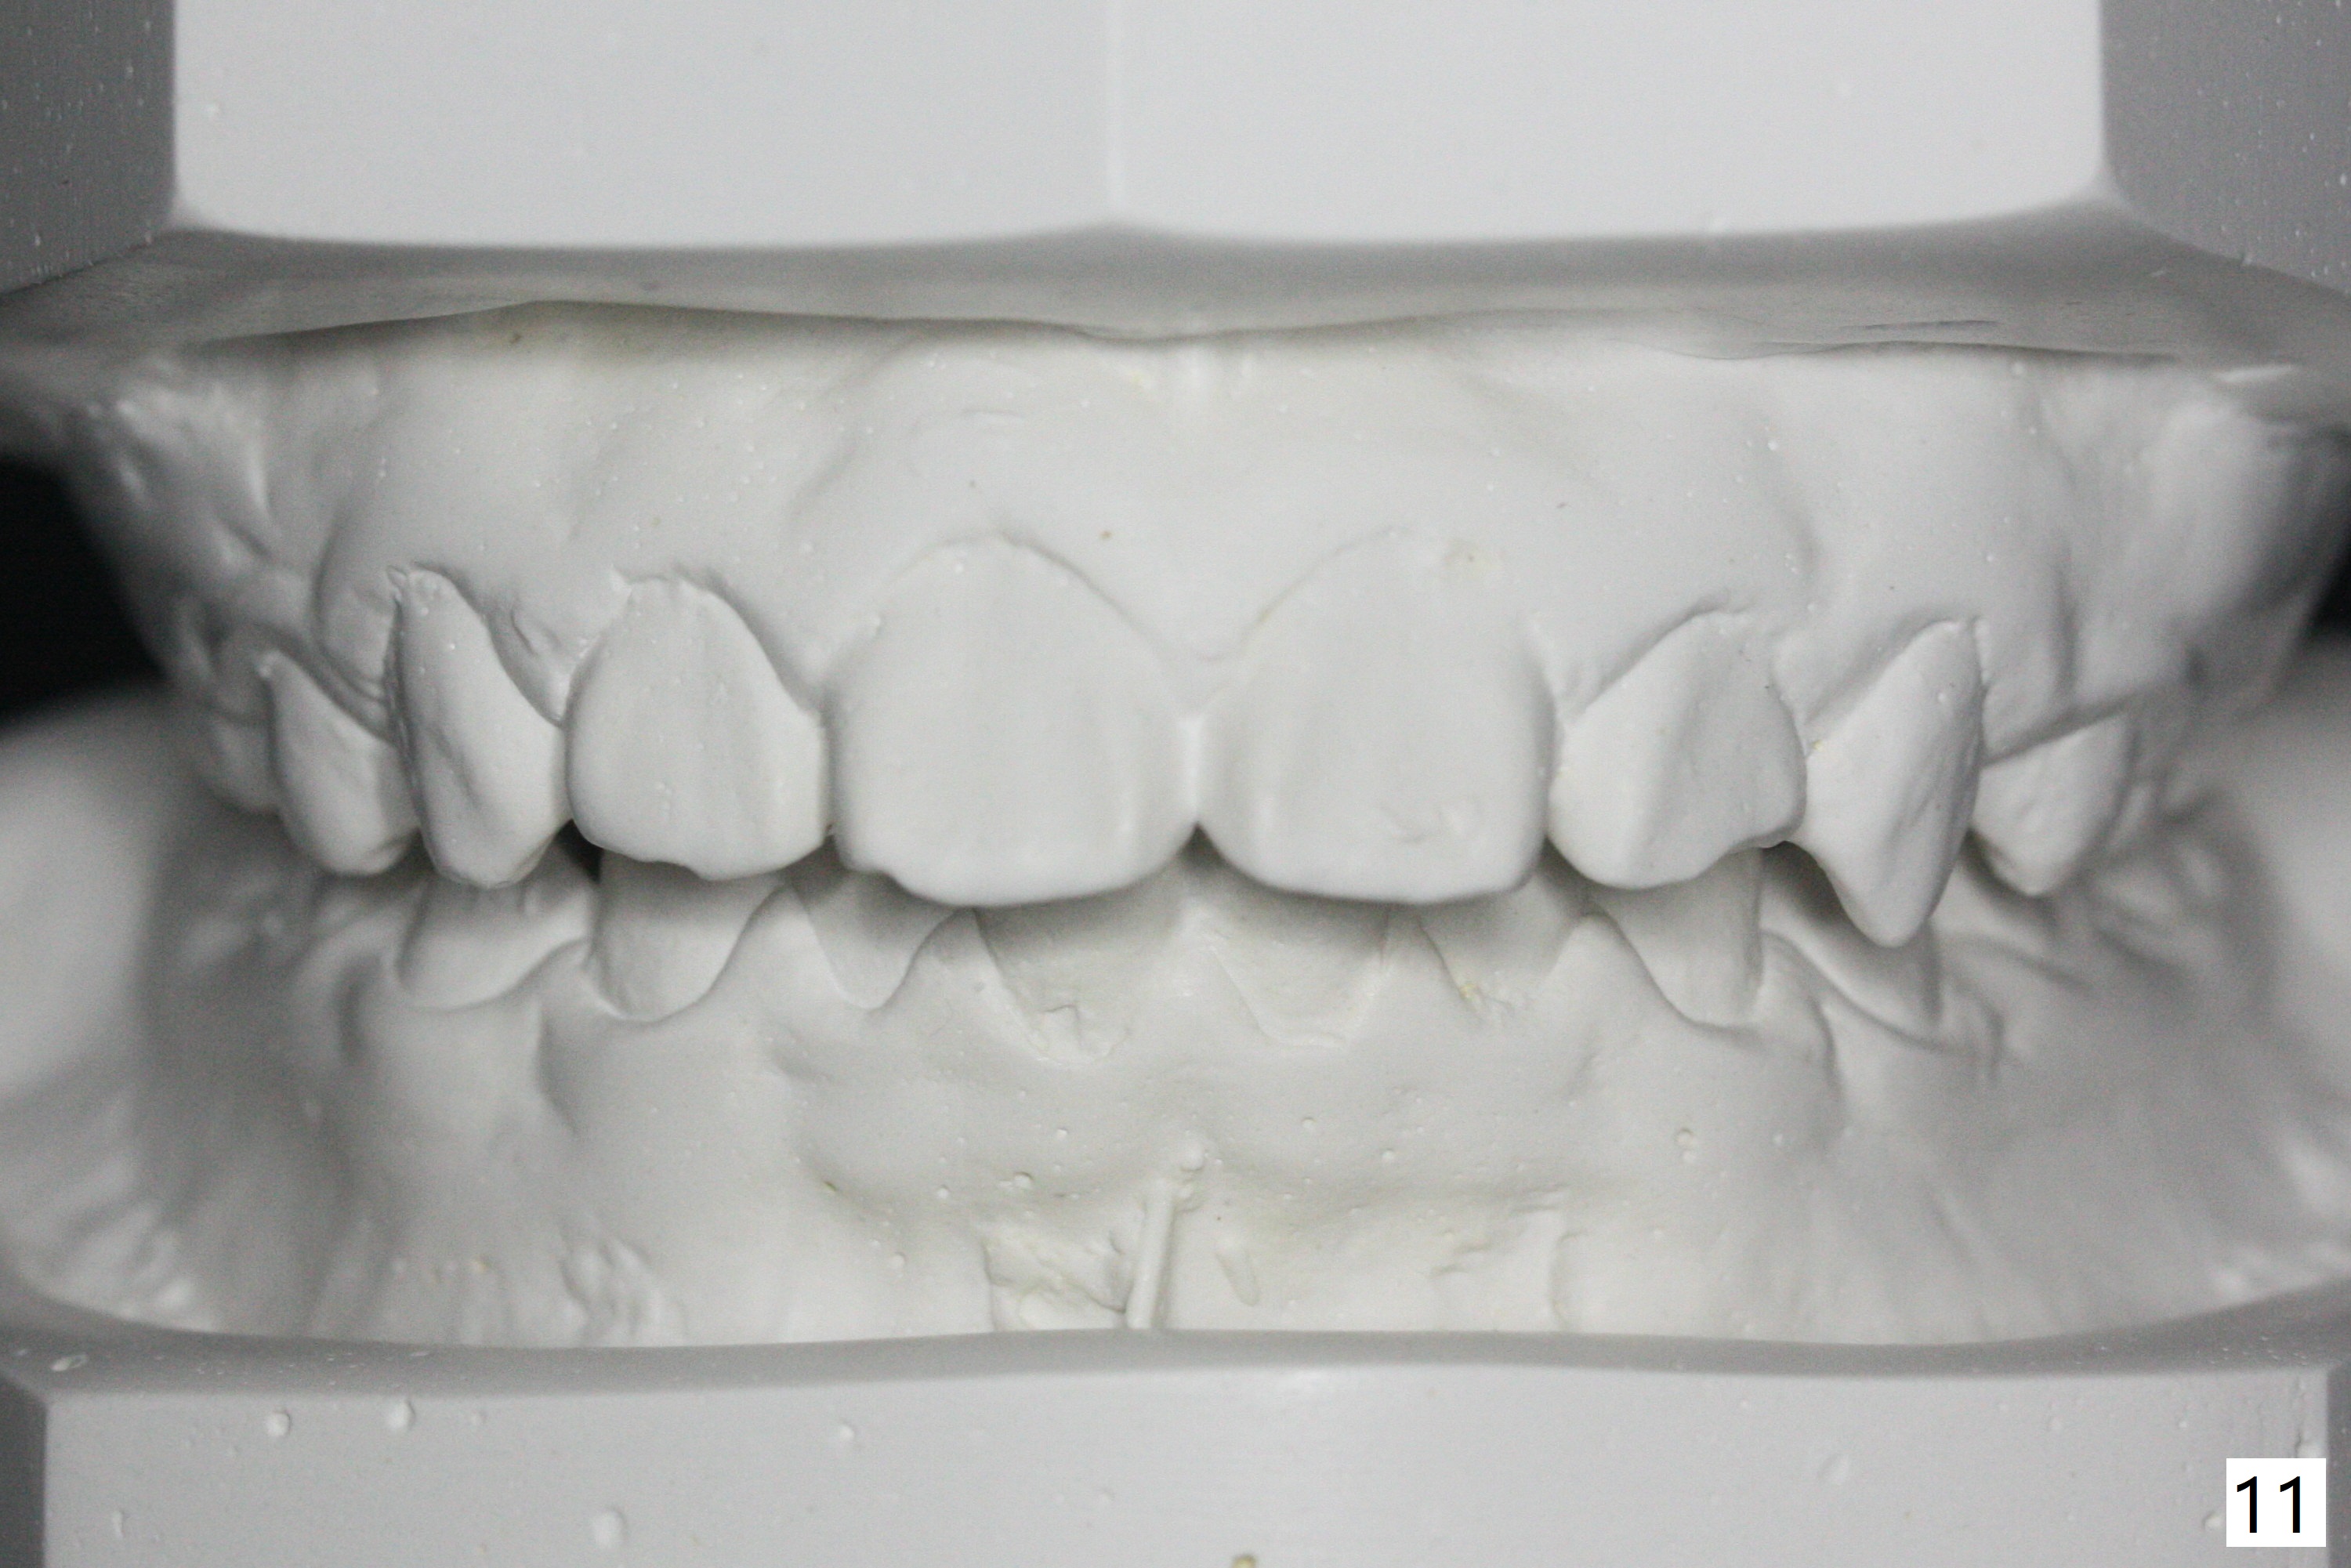

The mother of a 10-year-7-month old man requests treatment for the crowding lower incisors (Fig.14). The canines and molars are Class II by a half of a tooth (Fig.7,9,10,12). The dentition is mixed with E retention (Fig.13,14,16). Orthodontic treatment will start before E exfoliation for alignment and establishment of Class I occlusion as much as possible by distalizing U6s. Fine adjustment for intedigitation will be made when E exfoliate.